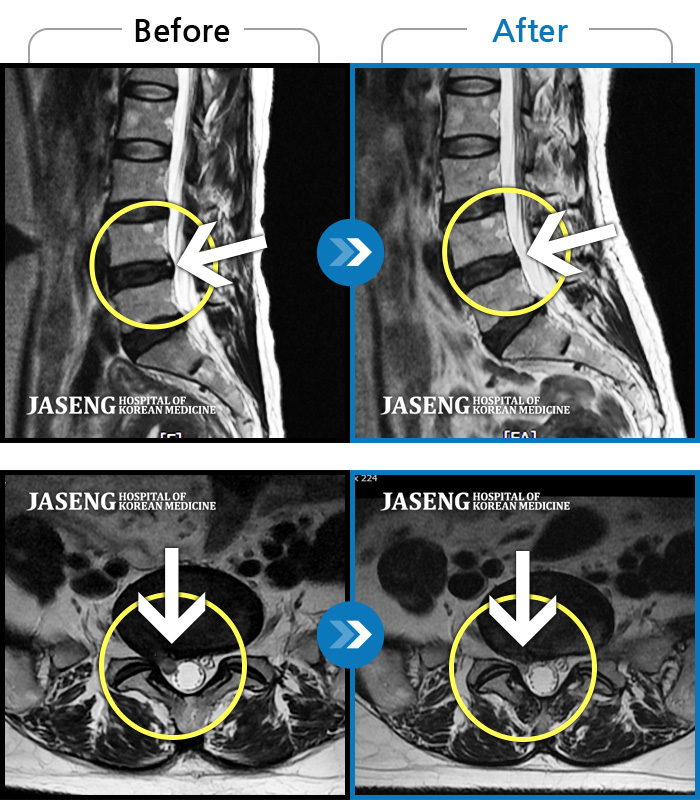

ȯںп Ǹ ǿ ԿǾ, ο ġ ۿ Ƿ ġḦ Ͻñ ٶϴ.